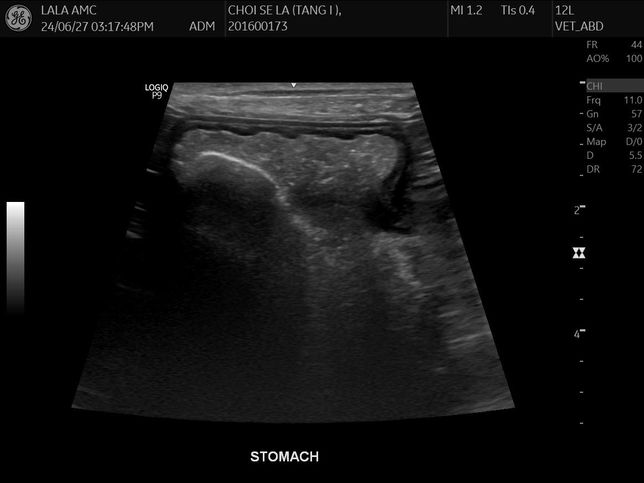

- 반려동물 건강반려동물Q. 강아지 몸속에 1.8cm물체가 있는것 같다는데 뭔지 모르겠어요건강검진 하면서 초음파를 찍었는데 강아지 몸속에 1.8cm 물체인지 뭔가가 보인다고 합니다 건강검진은 아무이상 없었구요의사선생님은 괜찮을것 같다고 했는데그리고나서 갈색토를 했구요 오늘아침에는 묽은변을 봤어요 (활력좋구요 사료먹는거 배변하는거는 이상없었습니다)자세한건 내시경을 해야한다고하네요..저것만봐서는 물체가 있는것같나요?엑스레이도 찍었는데 엑스레이로는 안보이는것같아요